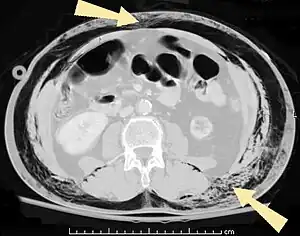

| An abdominal CT scan of a patient with subcutaneous emphysema (arrows) | |

Significant cases of subcutaneous emphysema are easy to diagnose because of the characteristic signs of the condition.[1] In some cases, the signs are subtle, making diagnosis more difficult.[13] Medical imaging is used to diagnose the condition or confirm a diagnosis made using clinical signs. On a chest radiograph, subcutaneous emphysema may be seen as radiolucent striations in the pattern expected from the pectoralis major muscle group. Air in the subcutaneous tissues may interfere with radiography of the chest, potentially obscuring serious conditions such as pneumothorax.[18] It can also reduce the effectiveness of chest ultrasound.[27] On the other hand, since subcutaneous emphysema may become apparent in chest X-rays before a pneumothorax does, its presence may be used to infer that of the latter injury.[13] Subcutaneous emphysema can also be seen in CT scans, with the air pockets appearing as dark areas. CT scanning is so sensitive that it commonly makes it possible to find the exact spot from which air is entering the soft tissues.[13] In 1994, M.T. Macklin and C.C. Macklin published further insights into the pathophysiology of spontaneous Macklin's Syndrome occurring from a severe asthmatic attack.